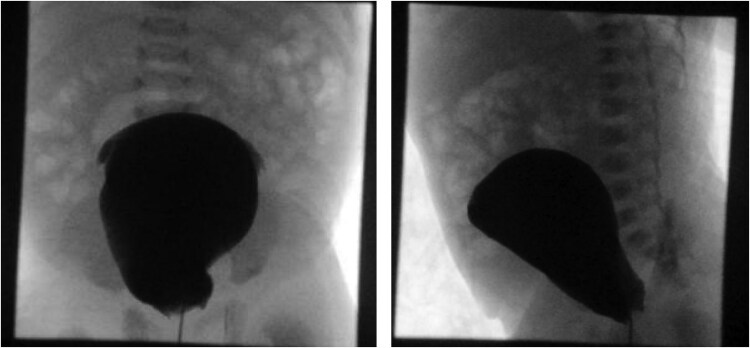

46,XY sex reversal 11 (SRXY11) is a rare and recently identified form of 46,XY difference in sexual development (DSD), caused by variants in the DEAH-Box Helicase 37 gene (DHX37). DHX37 is crucial for ribosome biogenesis, but its specific role in gonadal development remains unclear. The genital phenotype varies widely, ranging from typical female to typical male. We present a 46,XY infant with prenatal ultrasound findings of atypical genitalia. Amniotic fluid gene analysis revealed a known heterozygous pathogenic variant in DHX37, p.R308Q (c.923G>A), confirmed postnatally. The patient was born with markedly undervirilized genitalia with posteriorly fused labioscrotal folds, a single introitus, no clitoromegaly, and nonpalpable gonads. Laboratory evaluation at multiple points showed undetectable anti-Müllerian hormone (AMH) and inhibin B levels, elevated gonadotropin levels, and negligible testosterone levels. Clinical course was complicated by urine retention in the vagina and uterus and hydronephrosis requiring catheterization. Endoscopy revealed a urogenital sinus with separate urethral and vaginal openings and 2 cervices leading into 2 separate uteri suggestive of a bicornuate bicollis uterus. Laparoscopy revealed 2 intra-abdominal gonads adjacent to the fallopian tubes. Evidence for inheritance, penetrance, genotype-phenotype correlation, and risk of malignancy in SRXY11 is limited to case reports.